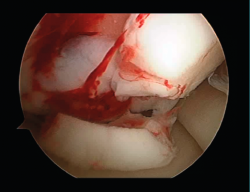

Figura 1. Imagen artroscópica de una lesión condral aguda de grado IV de Outerbridge del cóndilo femoral interno.

Figura 2. Imagen de la artroscopia de una lesión condral crónica de grado IV de Outerbridge en el cóndilo femoral interno.

La primera cirugía es una artroscopia de la articulación dañada. En ella, se valora la lesión condral que se va a tratar y se confirma si es subsidiaria de realizar la técnica de implante de condrocitos (Figuras 1 y 2). También se realizan otros procedimientos si son necesarios, como puede ser la reconstrucción del ligamento cruzado anterior, meniscectomías parciales, implantes de menisco, realineamientos de rótula, osteotomías, etc. Por último, se toma la muestra de cartílago de una zona de no carga (zona intercondílea o cóndilo femoral interno en su borde superior). La muestra se extrae con pinzas de biopsia o, en su defecto, con pinzas de discectomía. Se toman entre 3 y 4 fragmentos del tamaño de granos de arroz de cartílago sano (Figura 3). Esta biopsia se introduce en un bote estéril que contiene un medio de cultivo, DMEN (Figura 4). Se mantiene en el medio ambiente y se envía al laboratorio lo antes posible. Se debe rellenar un formulario (Figura 5), en el que marcamos la articulación, dónde se encuentra la lesión y el tamaño del defecto. La muestra, al ser recogida en el laboratorio, es procesada y puesta en cultivo. A las 4-6 semanas, dependiendo de cada caso, se tiene ya el cultivo preparado para el implante.